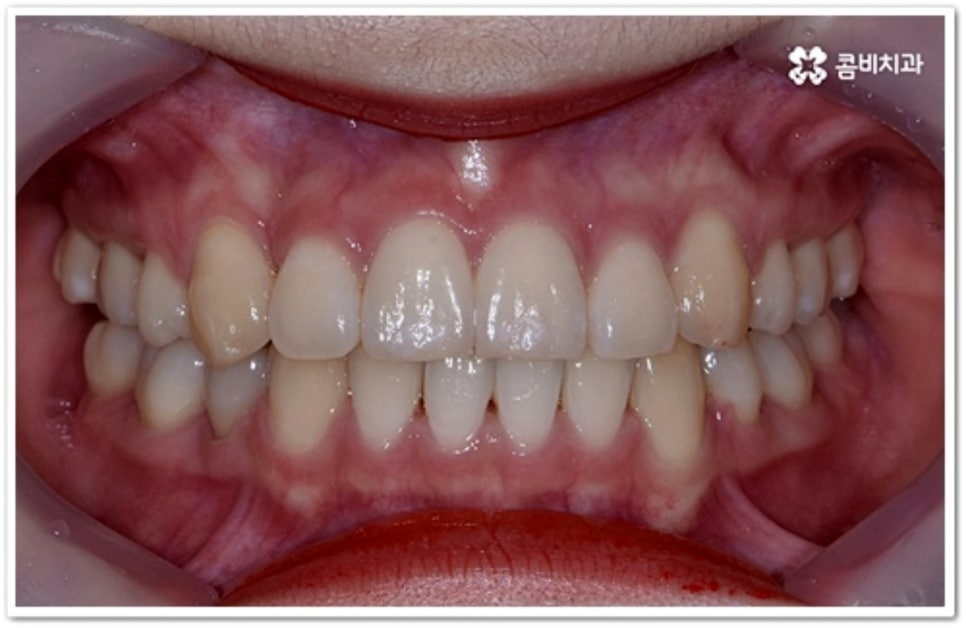

출처 아카이브 열기부정 교합의 일종인 덧니는 사람마다 다양한 원인으로 인해 발생하지만 보통 치아가 나올 공간이 부족하거나 치아 크기가 많이 커서 자기 자리에서 똑바로 나오지 못하고 이미 자리를 잡은 치아 앞 또는 뒤로 겹쳐 나오게 되면서 생기는 경우가 대부분이라고 할 수 있어요. 웃을 때 덧니가 살짝 드러나면 귀여운 인상을 주지만 실생활에서는 겹쳐진 치아 사이로 음식물이 자주 끼어 구강 질환을 유발하거나 저작 기능이 저하되는 등 불편함을 초래할 수 있습니다. 그렇기 때문에 치아 교정을 통해 가지런한 치열로 바로 잡아주실 필요가 있는데요.

이와 같이 덧니라고 해서 치료가 다 똑같이 진행되는 것이 아니기 때문에 개개인의 치열, 교합 및 골격 형태와 턱의 구조적 특징을 명확하게 파악할 수 있는 정밀 검진 장비와 다양한 케이스 경험이 풍부한 숙련된 의료진, 체계적인 사후 관리 시스템이 있는 곳에서 진료를 받으실 것을 권유드리고 있어요.

본 포스팅의 치료 케이스는 약 22개월의 치료 기간이 소요되었으며,

개인에 따라 출혈 및 부작용이 발생할 수 있고,

환자마다 치료 결과 및 기간이 상이할 수 있으므로,

정확한 치료 기간 및 치료 계획은

가까운 치과에서 상담을 받아보시길 권장 드립니다.